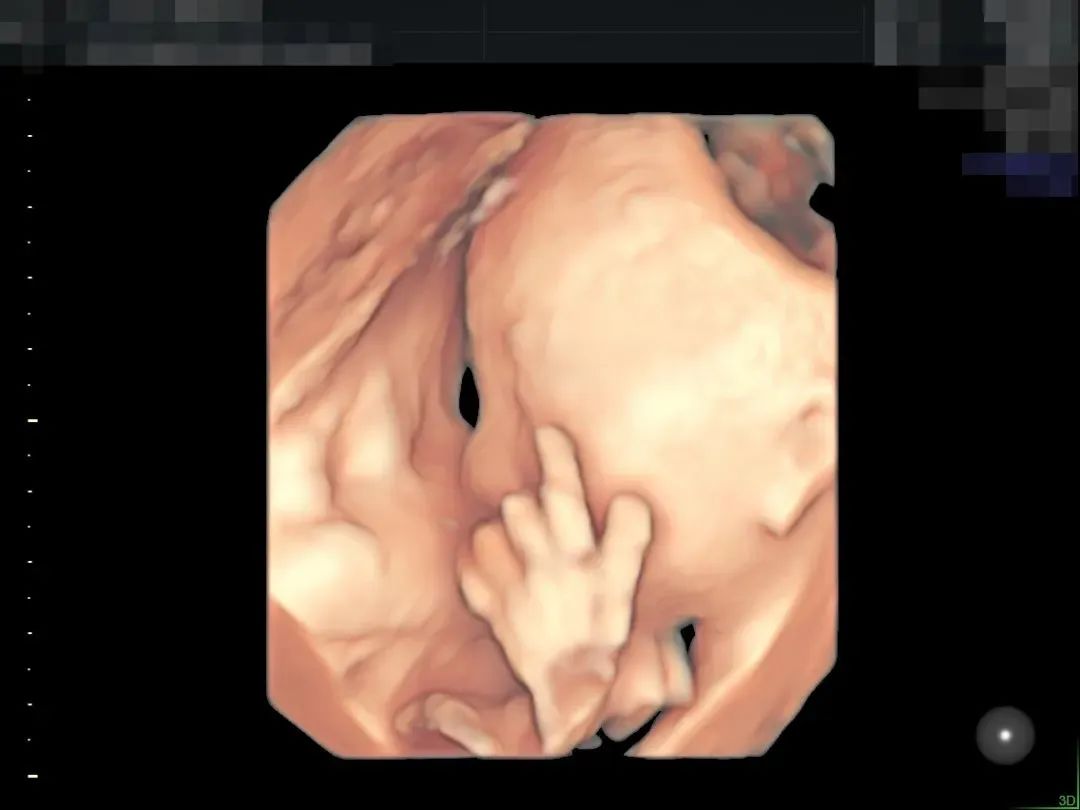

▲190斤孕妈王女士,不仅做了全面筛查,还留下了宝贵的胎儿影像,全家人都非常满意

▲孕妈肚皮脂肪较厚,羊水情况也不好,在和平进行了全面筛查